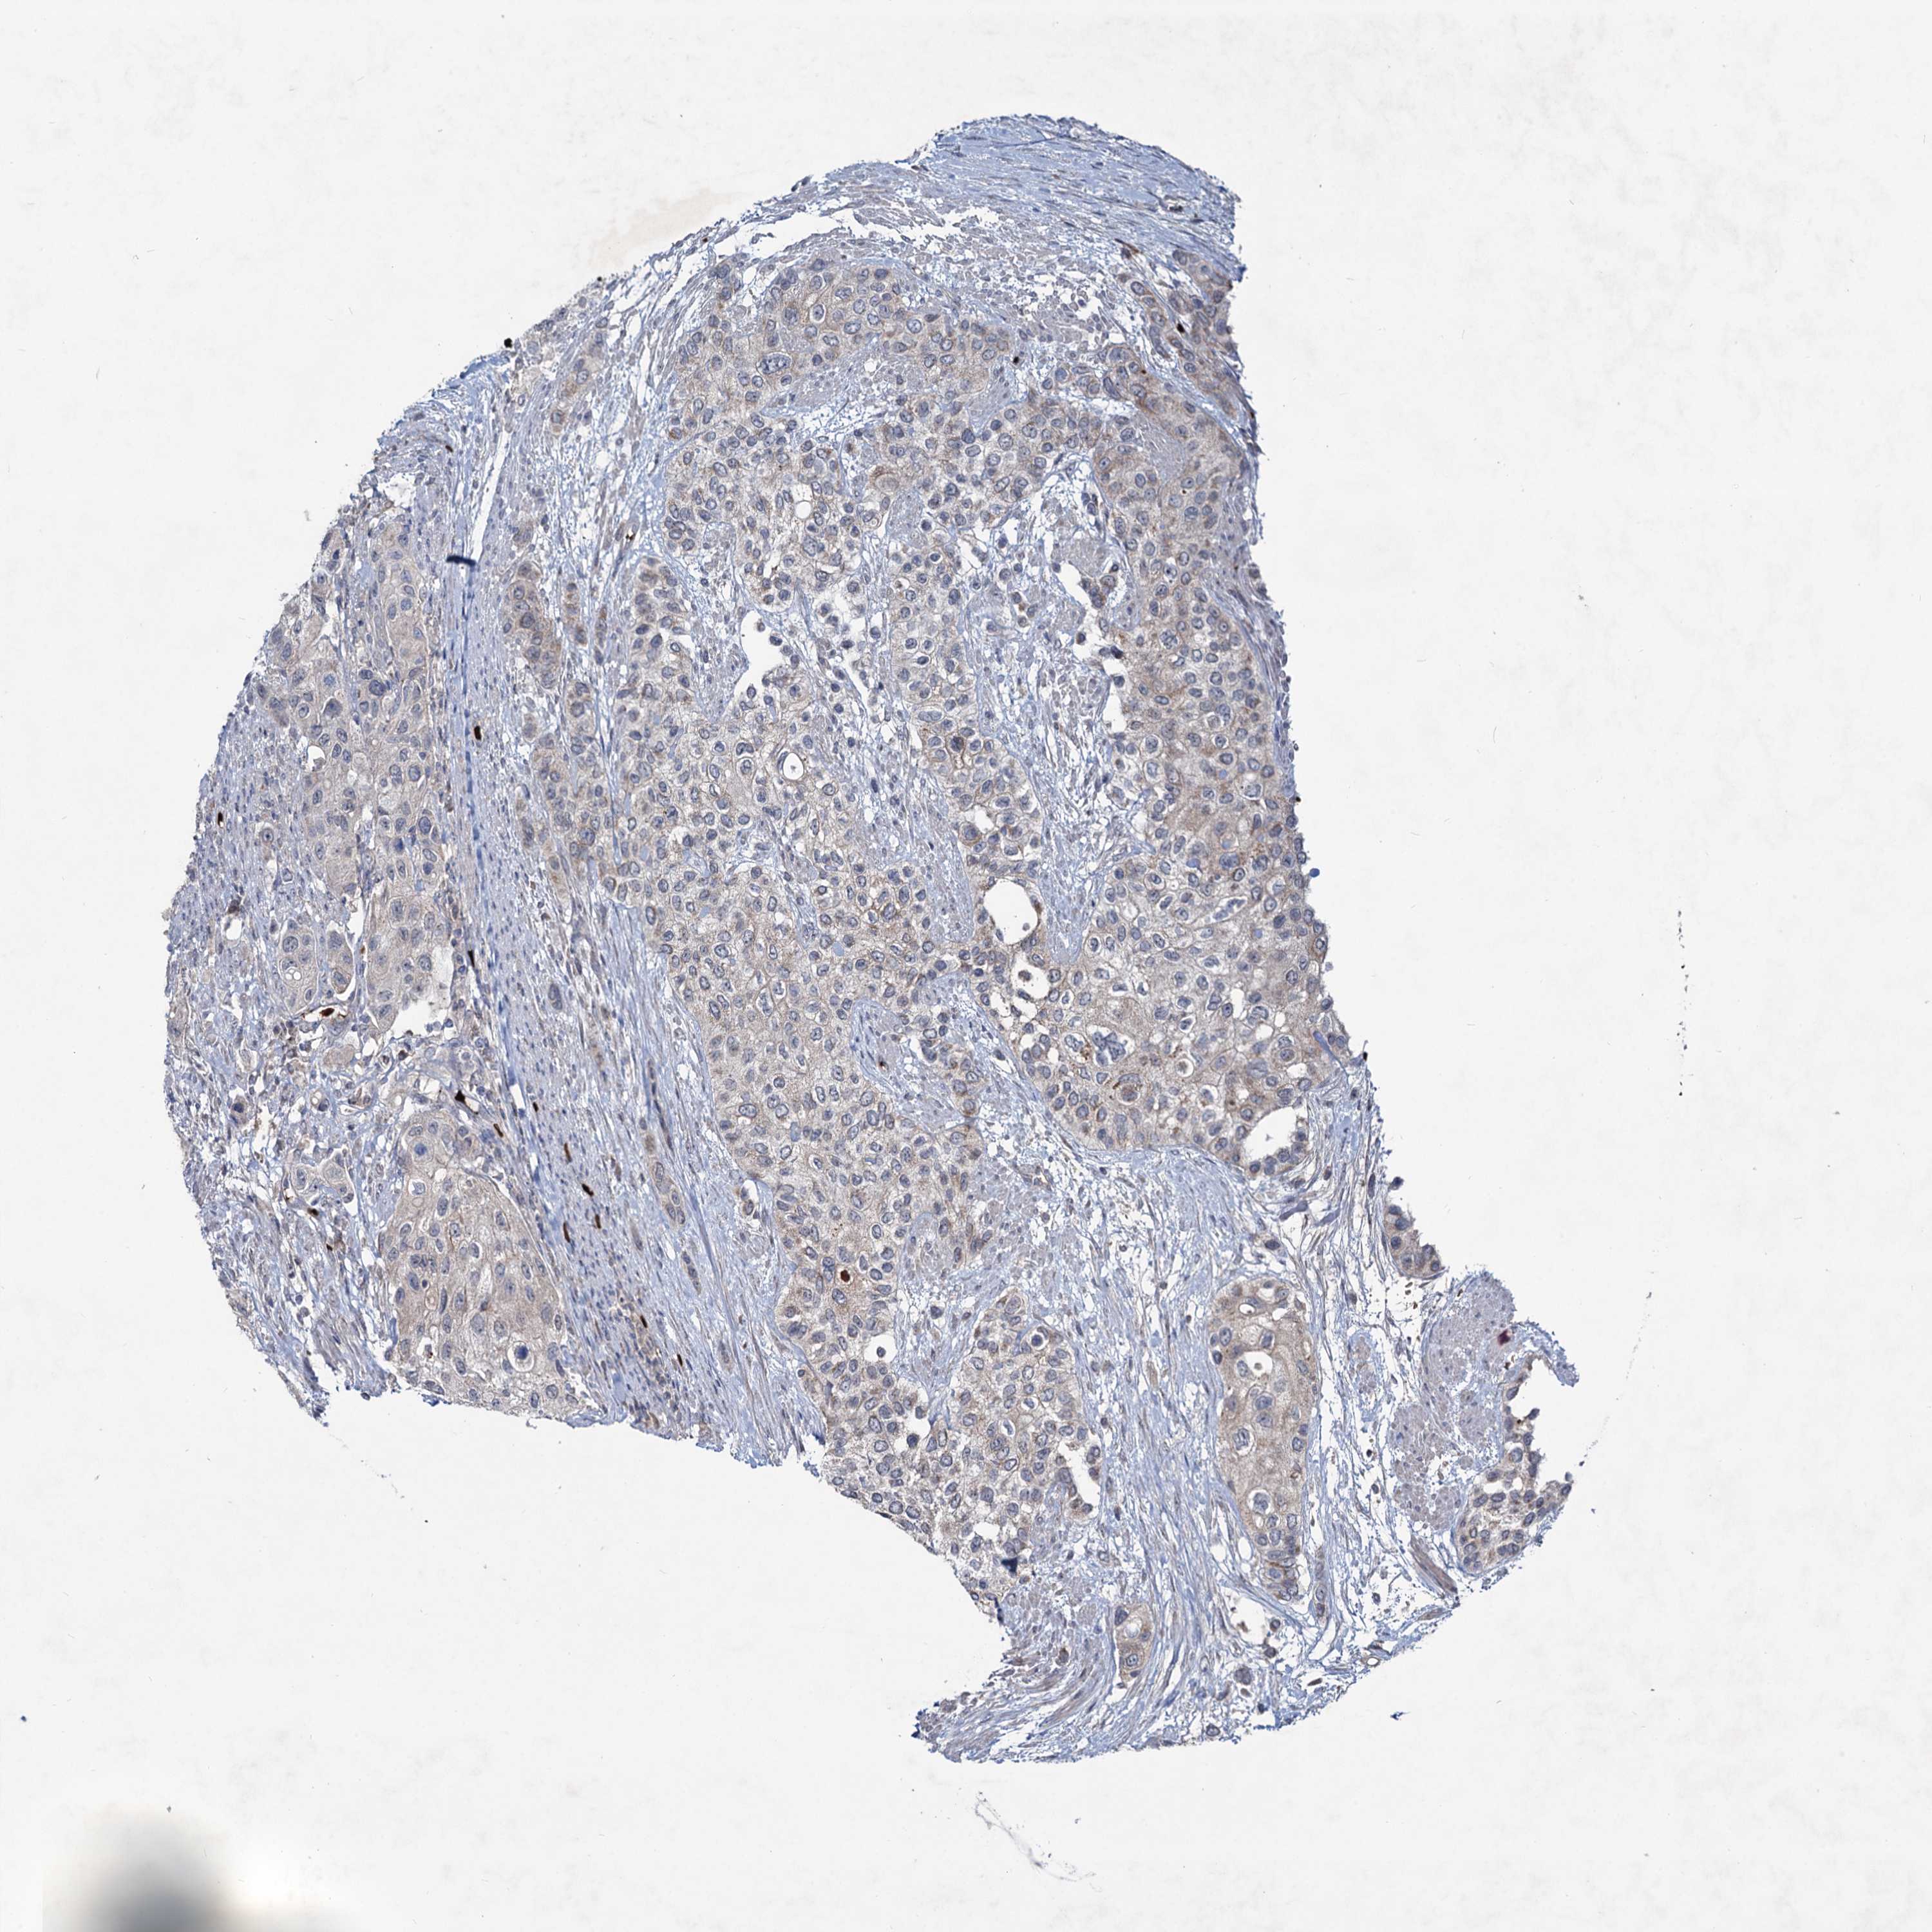

UROTHELIAL CANCER - Protein expressioni

A mouse-over function shows sample information and annotation data. Click on an image to view it in a full screen mode. Samples can be filtered based on level of antibody staining by selecting one or several of the following categories: high, medium, low and not detected. The assay and annotation is described here.

Note that samples used for immunohistochemistry by the Human Protein Atlas do not correspond to samples in the TCGA dataset.

Antibody stainingi

Antibody staining in the annotated cell types in the current human tissue is reported as not detected, low, medium, or high, based on conventional immunohistochemistry profiling in selected tissues. This score is based on the combination of the staining intensity and fraction of stained cells.

Each image is clickable and will lead to virtual microscopy that enables deeper exploration of all samples and also displays staining intensity scores, fraction scores and subcellular localization as well as patient and tissue information for each sample.

Antibody HPA039343

Antibody HPA040048

Urothelial carcinoma, High grade

Urothelial carcinoma, Low grade